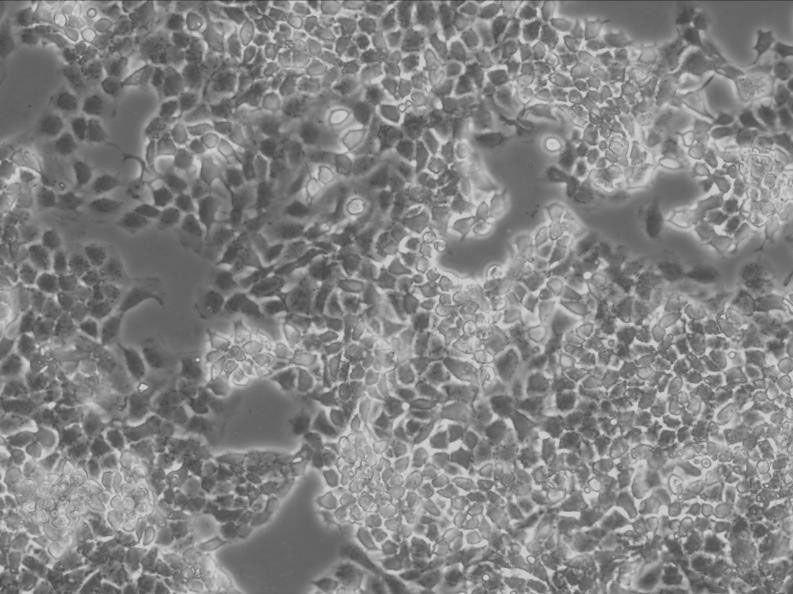

细胞生长:贴壁

细胞背景资料:胃癌;男性

细胞形态:上皮细胞样

细胞生长特性:贴壁